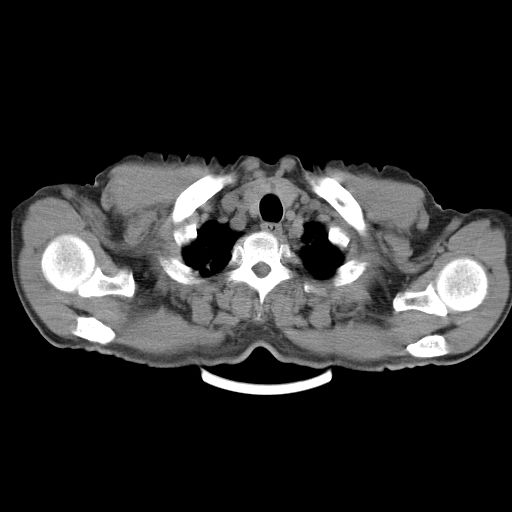

以下是引用心路寻觅在2010-3-1 10:23:00的发言:[br]1、考虑左肺上叶周围型肺癌[br]2、右上肺陈旧性病灶。[br][br][本贴已被 心路寻觅 于 2010-3-1 10:40:18 修改过]

以下是引用shuiyuan在2010-3-1 10:45:00的发言:[br]考虑左肺上叶中心型肺癌伴阻塞型炎症,邻近胸膜受侵。